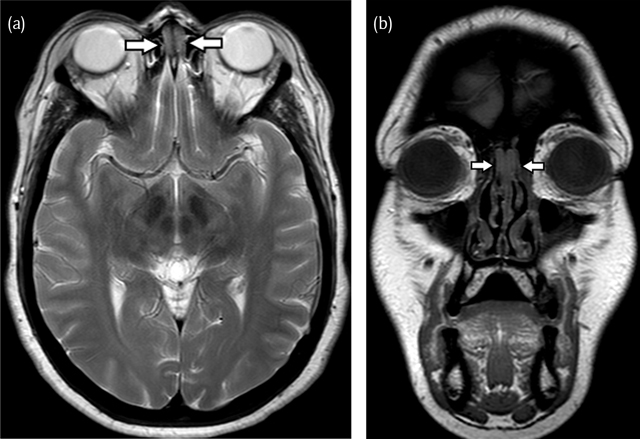

Figure 2

(a) On axial T2-weighted images and coronal T1-weighted (b) MR images the bilateral mass (arrows) appears iso-intense to white matter. The lesions are sharply delineated and do not involve or cross the cribriform plate.